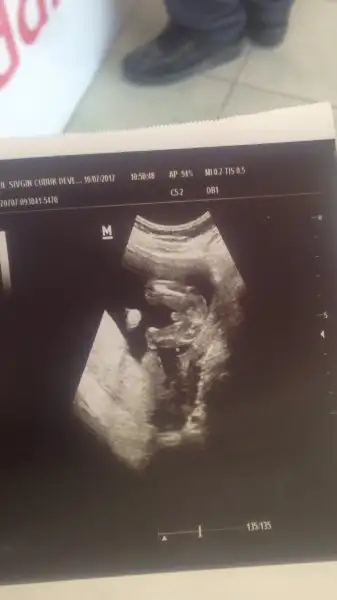

Arkadaslar gecen aranizdan birinin ultrason goruntusu boyleydi ya,instagramdan bu foto ve kiz.ilk erkek demisler,sonra anlasilmis

Cnm bu bebek 11 haftalıkmış belli bi zamana kadar bütün bebeklerin genitali aynı olurmuş sonraki haftalarda büyüdükçe kız veya erkek şeklini alırmış yani bu bebek daha çok küçük ve ayrıca yakından bakarsan pipi denilen şeyin ucu iki parça gibi ki bu da muhtemelen genitalin dudaklarıdır

Ya işte çıkıntı erkekde de kızda da oluyor onu karıştıyorlar bakın internetde nub teorisi var onu bi araştırın kızı erkek erkeği de kız zannediyorlar bide daha tam gelişmediği için kızdada böyle çıkıntı oluyor pipi gibi